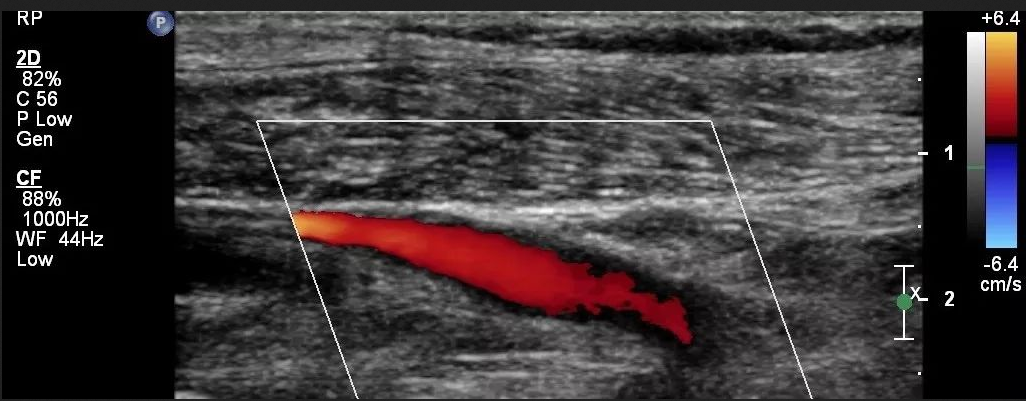

什么是彩色多普勒超聲?彩色多普勒超聲又稱彩超,是一種醫(yī)療設(shè)備,適用于全身各部位臟器超聲檢查尤其適用于心臟、肢體血管和淺表器官以及腹部、婦產(chǎn)等檢查診斷。它是以脈沖波多普勒為基礎(chǔ),用運(yùn)動目標(biāo)顯示器,自相關(guān)函數(shù)計算,數(shù)字掃描轉(zhuǎn)換、彩色編碼等技術(shù)達(dá)到對血流的彩色顯像。

①彩色多普勒超聲中顯示的紅色不一定是動脈,而藍(lán)色也不一定是靜脈。

②常規(guī)情況下,紅色代表的是朝向探頭的血流,藍(lán)色代表背離探頭的血流。

當(dāng)然,紅色代表朝向探頭,藍(lán)色代表背離探頭并不是一成不變的,可以通過機(jī)器進(jìn)行設(shè)置。另外彩色多普勒取樣框的角度也可以改變血流顯示的顏色,但為了更好的呈現(xiàn)彩色血流信號,取樣框與血管角度應(yīng)盡可能小。

彩色多普勒信號強(qiáng)度可以粗略反映血流的快慢,彩色信號明亮說明血流速度快,彩色信號暗淡說明血流速度慢。

①由于動脈具有搏動性,其在舒張期血流速度慢而呈較暗淡的血流信號甚至無血流信號,而收縮期血流速度較快,呈較明亮的血流信號,在動態(tài)觀察時,便可見動脈血流信號呈閃動出現(xiàn),彩色信號較明亮。

②靜脈血流速低,無收縮期、舒張期之分,因此血流信號是連續(xù)出現(xiàn)的,彩色信號較暗淡。

血流的性質(zhì)包括層流及湍流。層流的彩色血流信號顯示比較均勻,呈中央部亮度高、近管壁處亮度低的彩色信號;湍流則呈現(xiàn)五彩鑲嵌的血流信號等。